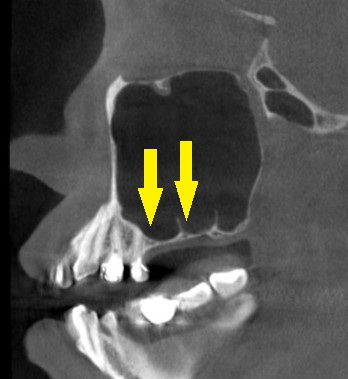

レントゲン、CTを撮影してみると、確かに骨は薄く、薄いところでは1mmあるかないかでした。

さらに骨の形態が複雑で、骨造成を行うにも、なかなかな難易度が高い状態でした。

それでも、患者様の強い希望がありましたので、他に方法はないと考え、まずサイナスリフトという、人工骨を上顎の空洞部分に填入して骨を増やす手術を、本日施行しました。

下の写真、下段右が、手術後のCTです。